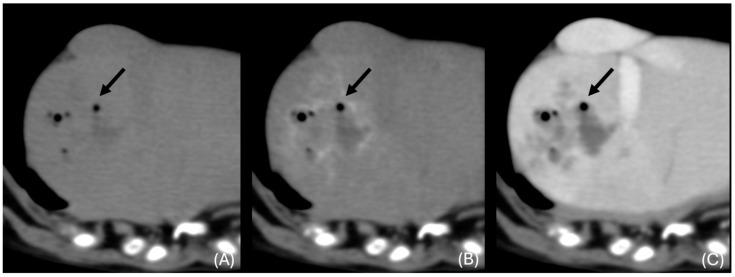

Bacterial liver parenchymal infections in dogs are rarely documented, and their imaging characteristics are scarce in the veterinary literature, especially in Computed Tomography (CT). This retrospective multicentric study aimed to describe the CT characteristics of parenchymal bacterial liver infection and abscessation in dogs and compare them with the human literature. Twenty dogs met the inclusion criteria. All dogs, except one, showed discrete hepatic lesions consistent with pyogenic liver abscess (19/20). A single case showed diffuse liver changes, which was diagnosed with granulomatous bacterial hepatitis (1/20). Multifocal lesions were associated with the presence of abdominal pain ( = 0.023). CT characteristics of pyogenic liver abscesses in our study resemble those described in the human literature, with multifocal (14/19) or single (5/19), round or ovoid (19/19), hypoattenuating hepatic lesions, which are better visualised in post-contrast images. Pyogenic liver abscesses can also show features such as the "cluster sign" (8/19), transient arterial segmental enhancement (6/10), rim enhancement (6/19), and intralesional gas (4/19). Additional CT findings, such as local lymphadenomegaly (18/20), peritoneal fat stranding (14/20), and peritoneal fluid (13/20), are also commonly observed.

犬细菌性肝实质感染鲜有文献记载,其影像学特征在兽医文献中也很罕见,尤其是在计算机断层扫描(CT)方面。这项回顾性多中心研究旨在描述犬肝实质细菌感染和脓肿形成的CT特征,并与人类文献进行比较。20只犬符合纳入标准。除1只犬外,所有犬均表现出与化脓性肝脓肿相符的离散性肝脏病变(19/20)。1例犬表现为弥漫性肝脏改变,诊断为肉芽肿性细菌性肝炎(1/20)。多灶性病变与腹痛有关( = 0.023)。我们研究中化脓性肝脓肿的CT特征与人类文献中描述的相似,表现为多灶性(14/19)或单灶性(5/19)、圆形或椭圆形(19/19)、肝脏低密度病变,在增强后图像中显示更佳。化脓性肝脓肿还可表现出“簇状征”(8/19)、短暂性动脉节段性强化(6/10)、边缘强化(6/19)和病灶内气体(4/19)等特征。其他CT表现,如局部淋巴结肿大(18/20)、腹膜脂肪条索征(14/20)和腹腔积液(13/20)也较为常见。